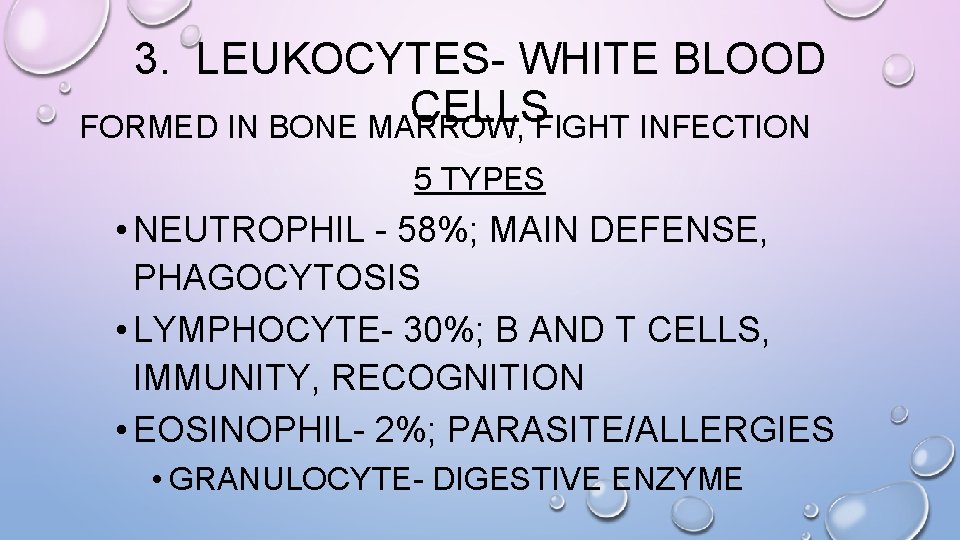

3. LEUKOCYTES- WHITE BLOOD CELLS FORMED IN BONE MARROW, FIGHT INFECTION 5 TYPES • NEUTROPHIL - 58%; MAIN DEFENSE, PHAGOCYTOSIS • LYMPHOCYTE- 30%; B AND T CELLS, IMMUNITY, RECOGNITION • EOSINOPHIL- 2%; PARASITE/ALLERGIES • GRANULOCYTE- DIGESTIVE ENZYME